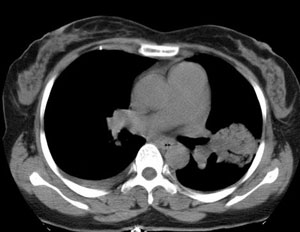

女性,30岁。

病史为胸痛20多天,无畏寒发热,无消瘦,无咳嗽咳痰。总之症状很逍遥。

临床以胸痛待查收住入院。

双肺野可见散在大小不等结节及肿块影,内密度不均匀,边缘部分清,部分欠清,纵隔未见明显肿大淋巴结.右侧胸腔少理积液.结合临床,考虑韦格肉芽肿可能吧,巨淋巴增生,结节病,特殊感染都要考虑.转移瘤临床不象.

本病例特点如下:

1.青年女性,以胸痛20多天就诊,无呼吸道及感染临床症状体征,无原发肿瘤病史;

2.肺ct表现为两肺多发大小不等结节影,大结节位于肺尖部,小结节多位于肺外带胸膜下,大结节内可见支气管充气征,周围可见月晕征(指在结节状或肉芽肿样病灶周围呈环形磨玻璃影),右肺门及腔静脉后可见小淋巴结,右侧胸腔内少量液体。

两肺散在分布大小不等的肿块及结节影,边缘毛糙,有分叶、毛刺,病灶密度不均匀,可见支气管充气相与空泡征。病变大多位于胸膜下,可见胸膜凹陷及胸腔积液。气管腔静脉间可见小结节影。

考虑肺真霉菌病;心脏增大,肺动脉增宽